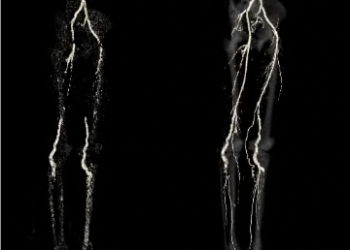

Boală rară cu calcificări arteriale dureroase

Dincolo de calcific?rile arteriale care apar în pl?cile de aterom, purchase doctor exist? o boal? rar? care se manifest? prin calcific?ri extinse la nivelul arterelor membrelor inferioare ?i capsulelor articulare de la mâini ?i picioare.

În 2008, US National Institutes of Health a pus la punct programul Undiagnosed Diseases Program (UDP) pentru a ajuta persoanele cu boli necunoscute. UDP a anunțat săptămâna aceasta prima descoperire a unei rare: a fost identificată baza genetică și moleculară a une afecțiuni caracterizate prin calcificări arteriale extinse care generează claudicație și durere în membrele inferioare. Boala, denumită “calcificare arterială datorită deficienței de CD73” este cauzată de mutații ale genei NT5E, care codifică CD73, ce convertește AMP la adenozină. Odată cu descoperirea mecanismului acestei boli rare, cercetătorii au identificat și un nou concept în biologia vasculară și anume că adenozina joacă un rol important în prevenirea calcificărilor arteriale. Deși aceste calcificări sunt diferite de cele care apar în boala aterosclerotică (calcificări coronariene, aortice) în sensul că se formează la nivelul mediei și nu în intimă, mecanismul producerii lor ar putea avea aplicații și în cardiologie. În SUA există doar 9 indivizi care suferă de această boală.

Calcificările arteriale apar ca urmare a slăbirii sistemelor inhibitorii și sunt dependente de nivelul de pirofosfat (inhibitor potent al calcificării) și de TNAP, tissue-nonspecific alkaline phosphatase (care degradează pirofosfatul). Deficitul de CD73 duce la reducerea adenozinei extracelulare cu amplificarea activității TNAP și scăderea pirofosfatului, care favorizează depunerile de calciu. Afectarea selectivă a arterelor membrelor inferioare ar putea fi legată de distribuția particulară a receptorilor de adenozină la acest nivel. Ca tratament, se încearcă agenți adenozin-like (dipiridamol, care inhibă recaptarea celulară a adenozinei), analogi de pirofosfat (bifosfonați) sau inhibitori de TNAP (lansoprazol).